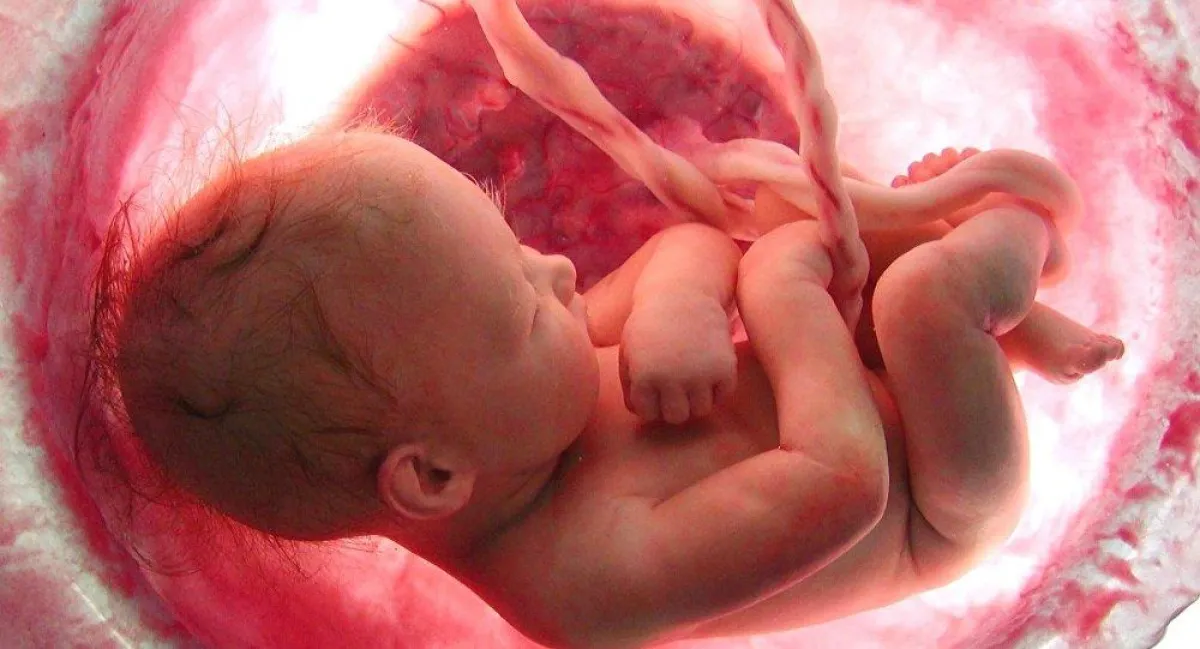

أجريت في بريطانيا عملية جراحية غير عادية لجنين أخرج من رحم أمه، ثم أعيد إلى رحمها بعد انتهاء العملية.

ووضع الطبيب أمام الأم ثلاثة خيارات، إما عدم التدخل في سير نمو الجنين، وبذلك سوف يكون المولود مشوهاً، أو إجراء عملية إجهاض، أو إخراج الجنين وإجراء عملية جراحية له، ثم إعادته إلى مكانه. فاختارت الأم الخيار الثالث مع كل تعقيداته وصعوبته.

ونجحت العملية رغم تعقيداتها وأعيد الجنين الى رحم أمه.